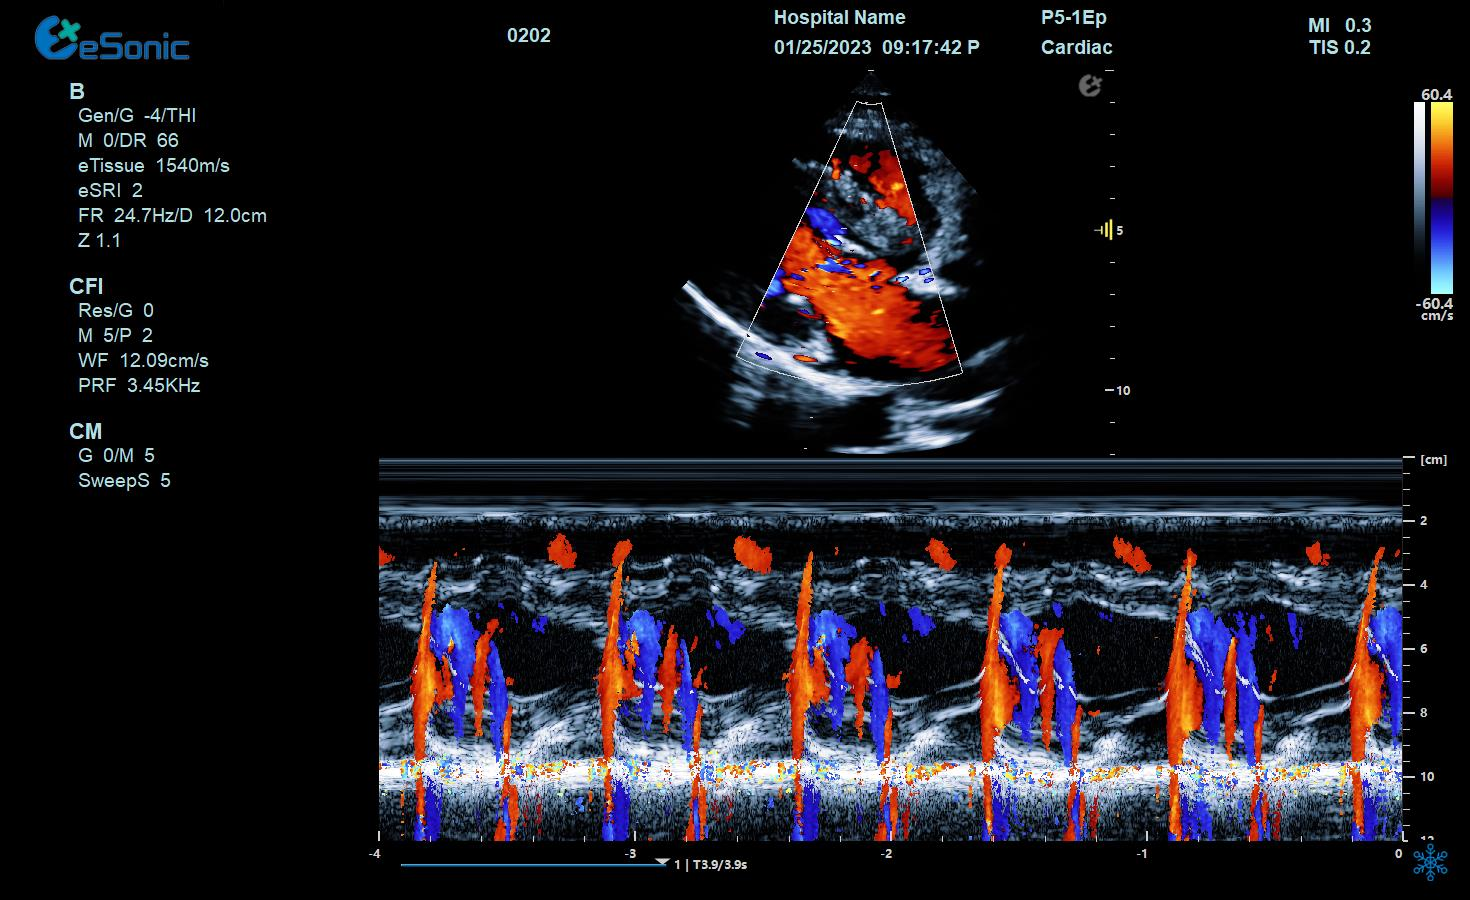

临床病例(二)

男性,82岁,临床诊断:风心病 房颤

超声表现:左房大,二尖瓣增厚、回声增强、运动僵硬;CDFI显示二尖瓣、三尖瓣、主动脉瓣返流信号。

风心瓣膜病二、三尖瓣关闭不全